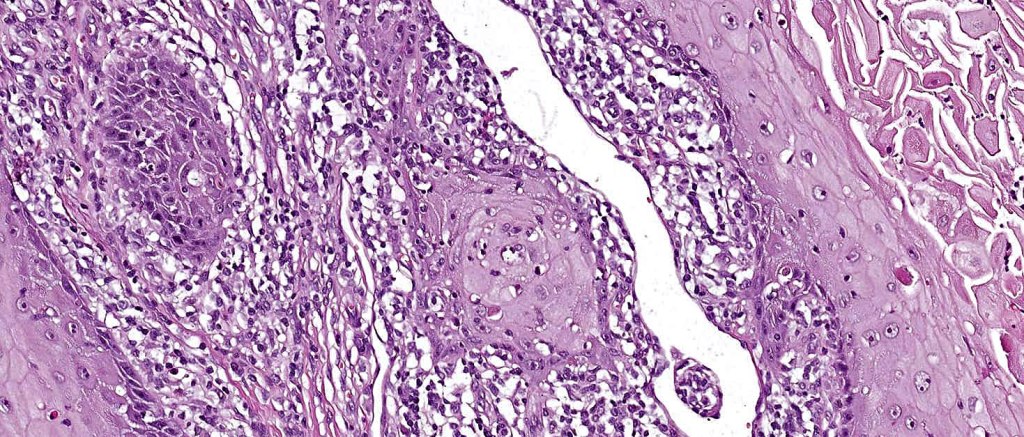

Histoloigcal features

•Often massive hyperkeratosis

•Epidermal verrucous hyperplasia

•Deeply penetrating bulbous processes with a pushing rather than infiltrating lower border

•Well differentiated epithelium characteristically having a ground glass appearance

•Marked tumor necrosis

•Intraepithelial abscesses

•Basally located mitoses